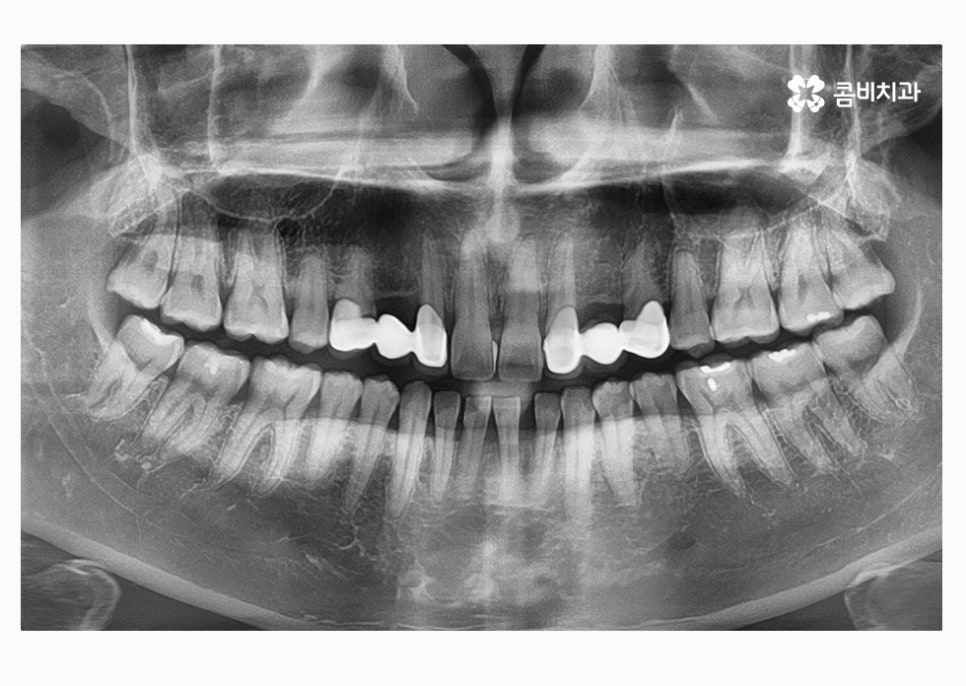

자세히 보시면 임시치아라는 것을 알 수 있고 엑스레이

사진을 보면 더 자세히 알 수 있습니다.